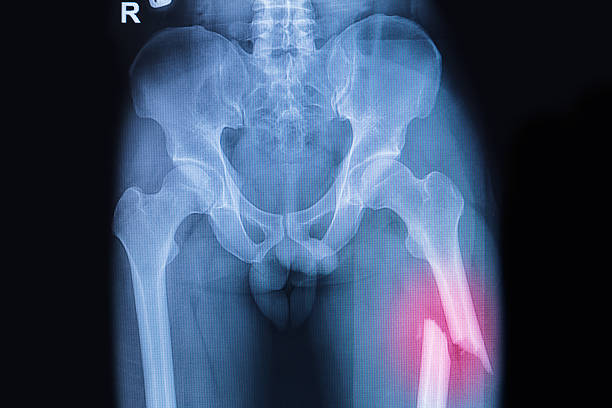

Perbedaan Patah Tulang Dan Retak Tulang Yang Sering Disalahpahami Banyak Orang

Perbedaan Patah Tulang Dan Retak Tulang, Istilah patah tulang dan retak tulang sering dipakai bergantian dalam percakapan sehari-hari. Akibatnya, banyak orang bingung membedakan tingkat keparahan, cara penanganan, hingga lamanya pemulihan. Ada yang menganggap retak tulang “ringan, cukup diurut”, ada juga yang panik berlebihan setiap kali mendengar kata patah. Kebingungan ini bukan sekadar soal istilah; salah paham bisa berujung pada penanganan yang kurang tepat, risiko pergeseran tulang, nyeri berkepanjangan, bahkan gangguan fungsi jangka panjang. Artikel ini mengupas perbedaan patah tulang dan retak tulang dengan bahasa sederhana, dari definisi, gejala, diagnosis, hingga langkah pemulihan yang aman.

Dalam istilah medis, hampir semua gangguan kontinuitas tulang sebenarnya disebut fraktur. Jadi, retak tulang dan patah tulang sama-sama termasuk fraktur; bedanya terletak pada derajat dan stabilitasnya. Retak tulang lazim menggambarkan fraktur tak lengkap (hairline atau garis halus) tanpa pergeseran berarti, sedangkan patah tulang kerap mengacu pada fraktur lengkap yang dapat bergeser, terfragmentasi, bahkan menembus kulit (fraktur terbuka). Perbedaan derajat ini memengaruhi keputusan klinis: apakah cukup imobilisasi dan terapi konservatif, atau perlu tindakan operasi untuk mengembalikan posisi dan stabilitas tulang.

Patah tulang menggambarkan fraktur lengkap yang memutus kontinuitas tulang. Potongan tulang dapat bergeser (displaced), membentuk sudut, memendek, atau terfragmentasi. Terkadang patah bisa tertutup (kulit utuh) atau terbuka (tulang menembus kulit), yang tentunya meningkatkan risiko infeksi dan membutuhkan penanganan lebih agresif.

Pada patah tulang, variasinya lebih beragam: transverse (garis lurus melintang), oblique (serong), spiral (berputar karena torsi), comminuted (terfragmentasi), impacted (saling menekan), hingga open fracture (menembus kulit). Pada anak, greenstick fracture (patah sebagian, seperti ranting muda) dan buckle/torus (penekukan korteks) sering terjadi karena tulang masih elastis.

Patah tulang biasanya lebih dramatis: nyeri hebat, bengkak nyata, memar, deformitas (bentuk anggota tubuh tampak tidak normal), krepitasi (rasa berderak), hingga kehilangan fungsi menumpu/meraih. Pada fraktur terbuka terdapat luka yang menganga dengan risiko perdarahan dan infeksi.